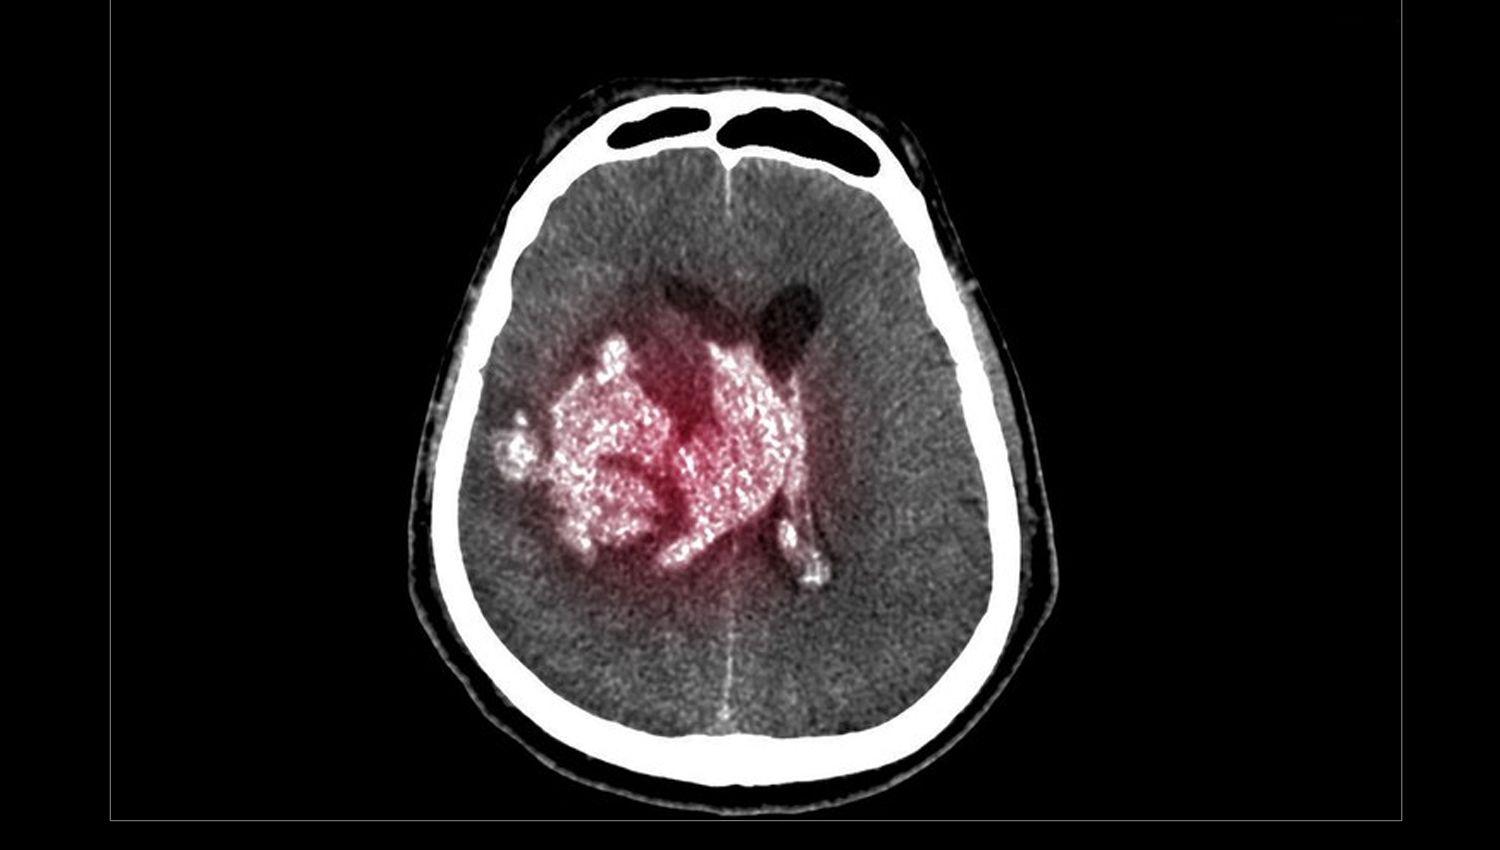

“El hematoma subdural es una acumulación de sangre en el espacio que está entre las dos membranas que cubren el cerebro”, explicó Alejandro Andersson (MN 65.836), neurólogo y director médico del Instituto de Neurología Buenos Aires.

“Los síntomas incluyen dolor de cabeza no habitual, náuseas, vómitos y sueño. Uno puede sufrir confusión, lentitud mental y también trastornos del lenguaje y problemas para mover alguna parte del cuerpo”, agregó Andersson. “Se diagnostica con una resonancia magnética o tomografía, y en general se actúa quirúrgicamente haciendo un drenaje. Todo depende del tamaño que tenga, hay pequeños o grandes, y el grado de urgencia depende de cada caso. En algunas situaciones se reabsorben solos, sin intervención quirúrgica”, sostuvo.